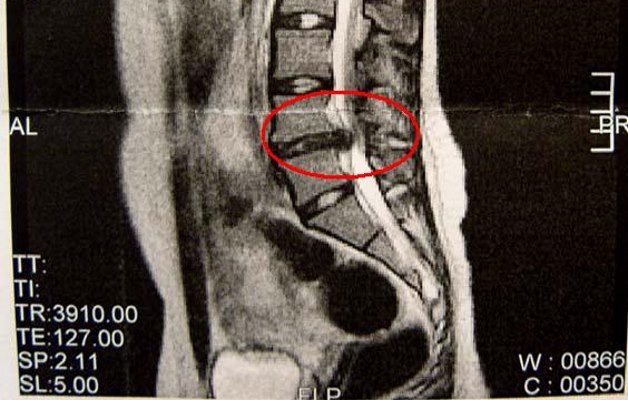

Чтобы уточнить диагноз, после беседы, визуального и пальпаторного обследования больного отправляют на аппаратную диагностику:

- Магнитно-резонансную томографию – назначается в случаях, когда другие методы дали спорный результат или вообще мало что показали. МР-картина патологии самая точная, однако этот вид диагностики и самый дорогостоящий.